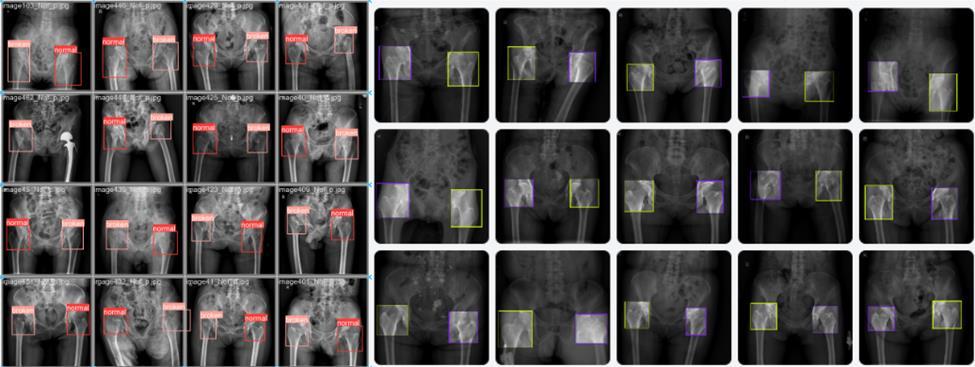

Fig 4. Example of femoral neck fracture detection on X-ray images left side predicted images right manually labeled images.